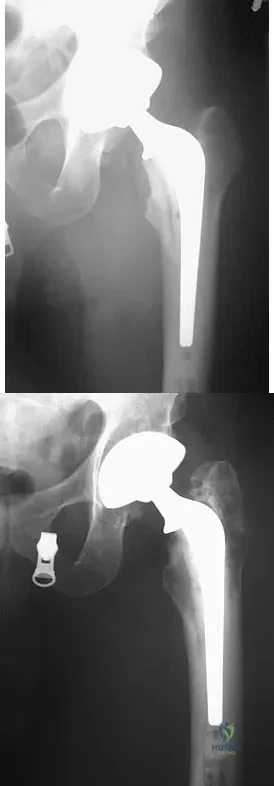

Question 17

A patient who underwent primary total hip arthroplasty 7 years ago that resulted in excellent pain relief and a normal gait now reports pain and a limp. Postoperative and current AP radiographs are shown in Figures 2a and 2b. What is the most likely cause of the pathology seen?

Explanation